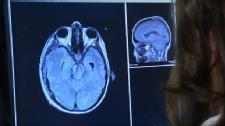

Alzheimer's disease is the most common form of dementia in adults. A degenerative disease, it affects areas of the brain that control thought, memory and language. Though the disease begins with people easily forgetting events or names of others, it progresses to difficulties with speaking, reading or writing. People may forget how to do basic tasks, become anxious or aggressive, and wander from home.